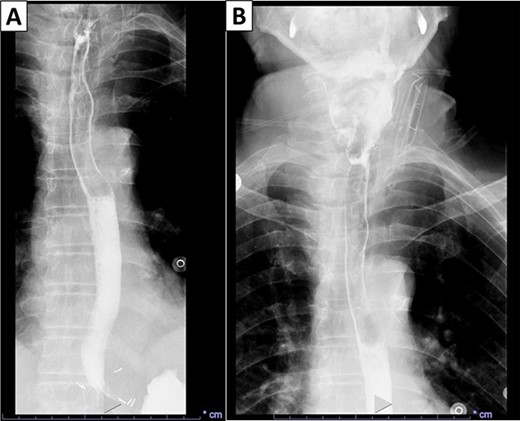

Gross examination revealed a fungating, exophytic, ulcerated, firm mass measuring 3.2 × 2.5 × 1 cm with a white cut surface involving the full thickness of the esophageal wall and grossly abutting the serosal surface. Microscopic examination showed a moderately differentiated SCC, invading the submucosa (Fig. 3). The surgical margins of resection were free of carcinoma and one cervical lymph node was identified and it showed no metastatic carcinoma. Postoperatively, the patient did well with no reported complications. An X-ray esophagogram was done showing no postoperative leak and no residual ZD (Fig. 4). He was referred to a hemato-oncologist for further management.

X-ray esophagogram performed postoperatively. No postoperative leak and no residual ZD were seen.